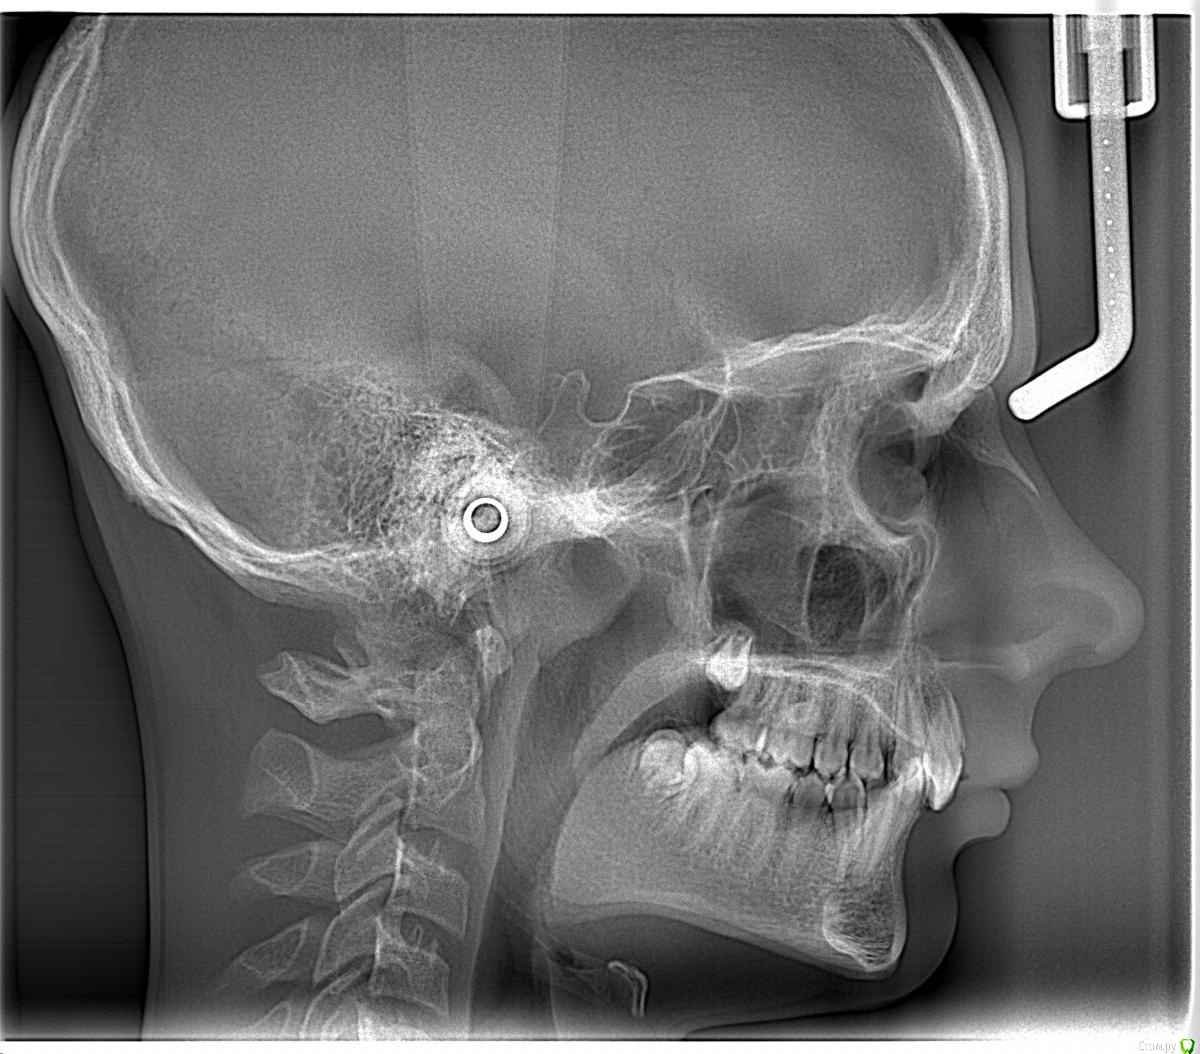

Opdihatop Опубликовано 24 октября, 2017 Поделиться Опубликовано 24 октября, 2017 И еще раз здравствуйте! Сразу хочу презентовать еще одного мальчика. Лично я такого еще не видел, а потому хочу понять, что тут делать. Думаю, невооруженным взглядом видно гипертонус и гиперплазию массетеров и гиперплазию углов н/ч из-за этого. Из-за чего это может быть и что тут делать? Как расслабить и что вообще делать с мышцами? Слать ли на сцинтиграфию (мало ли, может рост продолжается)? Есть ли шанс повысить прикус или такие мышцы все равно вколотят? Члх или нет? Заранее спасибо! Ссылка на комментарий

Brigita Опубликовано 24 октября, 2017 Поделиться Опубликовано 24 октября, 2017 (изменено) рост продолжается. по позвонкам можно посмотреть. даже не пик еще.а с мышцами... ну однозначно с какого то функционального аппарата начать надо... миомассаж редко где можно найти. да он и как припарка тут. Аппаратное расслабление если только. А вообще он на спортсмена похож, на футболиста. Изменено 24 октября, 2017 пользователем Brigita 1 Ссылка на комментарий

krokomot Опубликовано 25 октября, 2017 Поделиться Опубликовано 25 октября, 2017 Выкладывайте кт, сильно сомневаюсь что повышенный тонус массетер привел к гиперплазии углов. Перестройка да, гиперплазия нет. Ссылка на комментарий